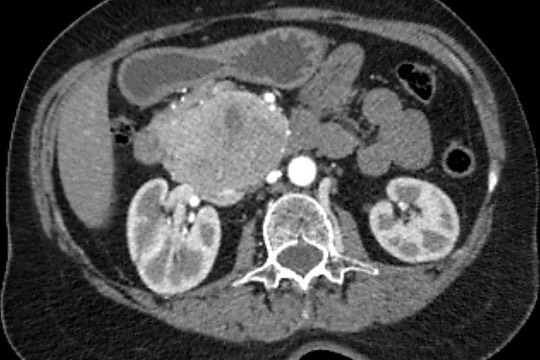

«Միքայելյան» համալսարանական հիվանդանոցում հերթական բարդ վիրահատությունն է իրականացվել, հեռացվել է ենթաստամոքսային գեղձի գլխիկի մեծ ուռուցք ավելի քան 10սմ տրամագծով, որը սերտ հպված էր միջընդերային զարկերակին և երակին:

Առհասարակ ենթաստամոքսային գեղձի գլխիկի մեծ չափի ուռուցքները համեմատաբար քիչ են հանդիպում: Առավել քիչ են հանդիպում այն դեպքերը, երբ գեղձի գլխիկի մեծ չափերի ուռուցքը չի առաջացնում մեխանիկական դեղնուկ: Համալսարանական հիվանդանոցի Վիրաբուժության կլինիկա է դիմել 62 տ. կին՝ գանգատվելով ցավից և ծանրության զգացումից վերորովայնային (էպիգաստրալ) շրջանում:

Հեռացված հյուսվածքի հետազոտությամբ հայտնաբերվել է ենթաստամոքսային գեղձի գլխիկի նեյրոէնդոկրին ուռուցք: